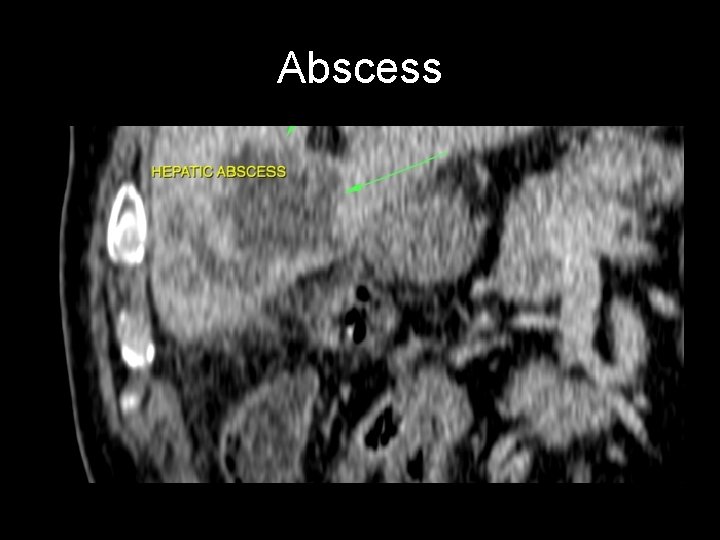

And…. If Murphy - - or the gallbladder is normal ? Differential diagnosis for acute cholecystitis includes: • • • choledocholithiasis pancreatitis peptic ulcer disease acute hepatitis liver abscess

Abscess